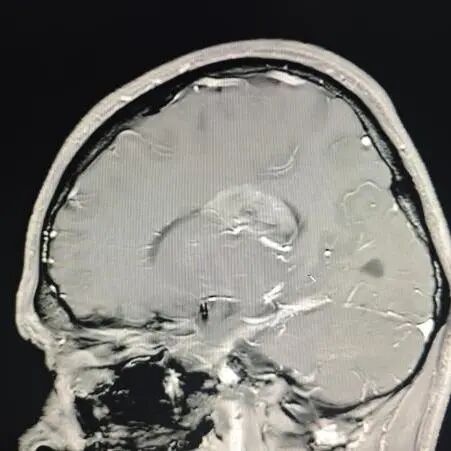

陆路副主任医师接诊后,为晓华做了详细检查。检查结果并不乐观:两年间,患者的肿瘤迅速生长至4厘米,挤压着左侧脑室后角空间。

"建议尽快手术!"诊室里,陆路副主任医师指着CT影像严肃地说道,"患者颅内的4厘米肿瘤已紧密压迫神经传导通路,若不及时处理,很可能导致脑脊液循环受阻,进而引发脑积水或肢体功能障碍。肿瘤每天都在生长,拖延只会让手术难度成倍增加。"这番解释让患者和家属深刻意识到病情的紧迫性。